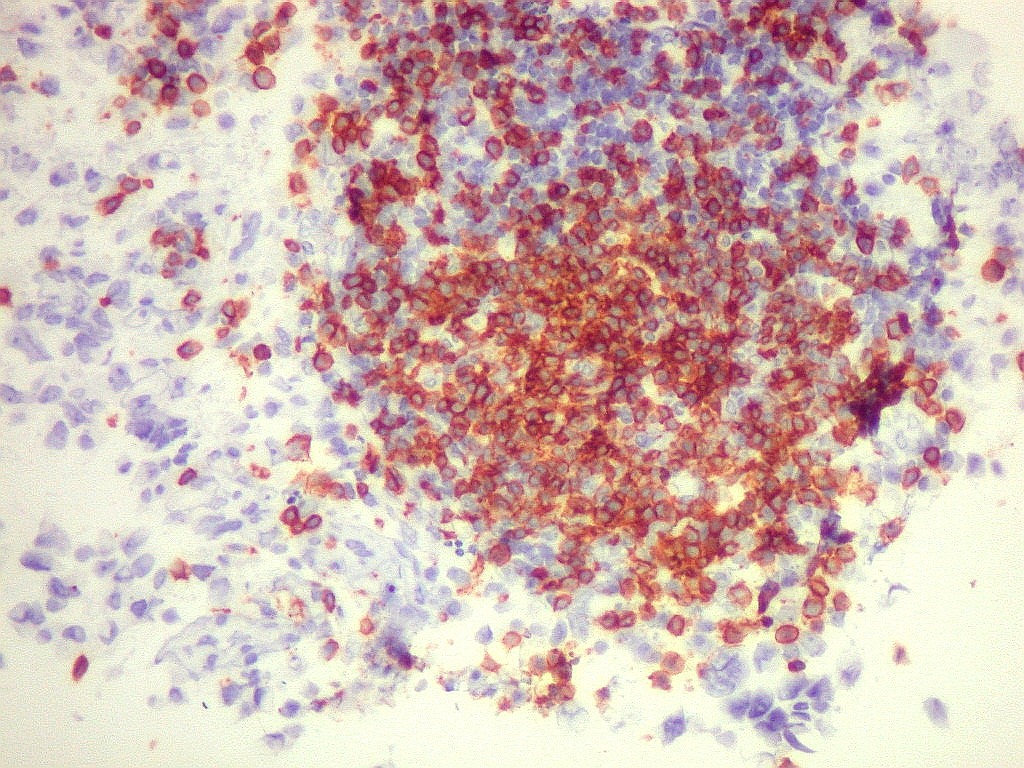

Tumor teratóide rabdóide atípico de III ventrículo.

7.  CD3, CD20, CD68, CD34

CD68.        Marca numerosos macrófagos no tumor, indicando alto turnover celular e  morte de muitas células neoplásicas, que são fagocitadas pelos macrófagos.

CD34.      Positivo só nos vasos, mostra  capilares bem distribuídos.  Células neoplásicas são negativas.